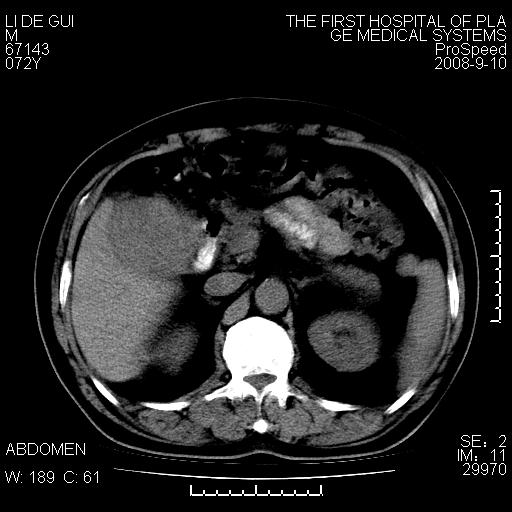

标题: CT17988:腹部肿块两年,肿块大小无变化,患者无不适,自我 [打印本页]

标题: CT17988:腹部肿块两年,肿块大小无变化,患者无不适,自我

胆囊占位性病变(黄色肉芽肿性胆囊炎?)。

考虑-----胆囊血肿机化或胆囊癌或腺肌增生症------增强

胆囊占位性病变,增强。

十二指肠的间质瘤